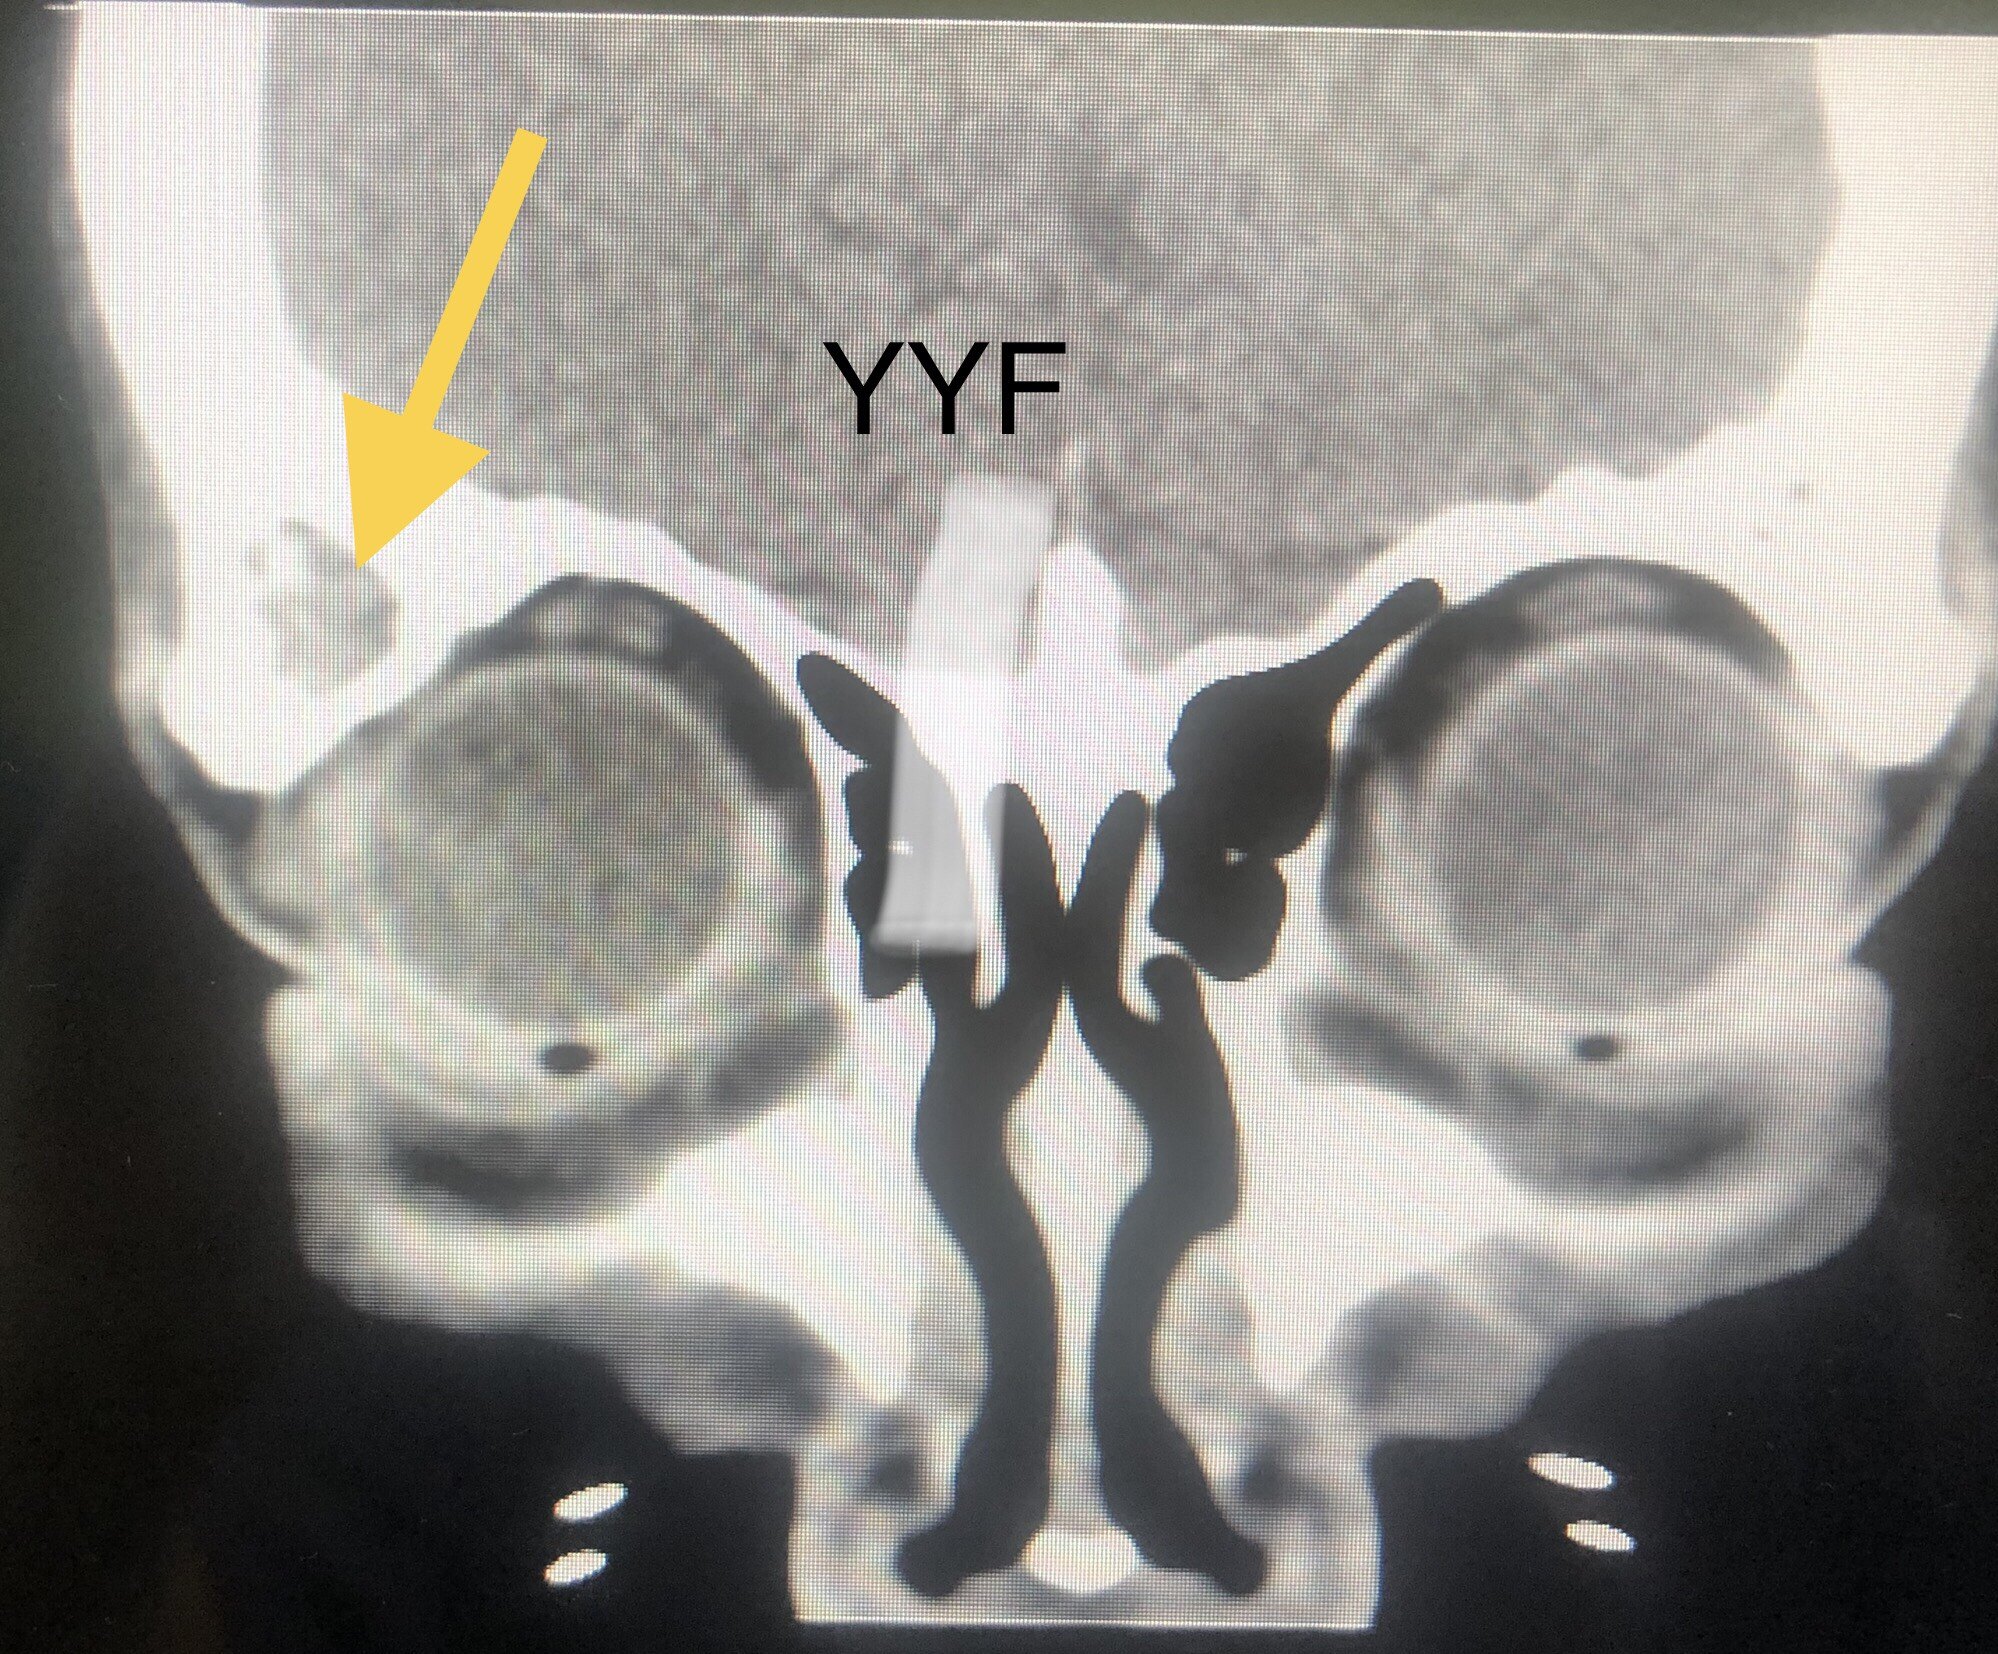

眶骨内低密度病灶

本例患者,对比双侧眼眶,可见右眼外上方骨壁增厚,骨性结构内有低信号病灶,

病灶无论在CT和核磁共振上都会显影,考虑到疼痛症状始终不缓解,最终决定手术明确性质。

骨质增厚尚可,黄色箭头为增厚处